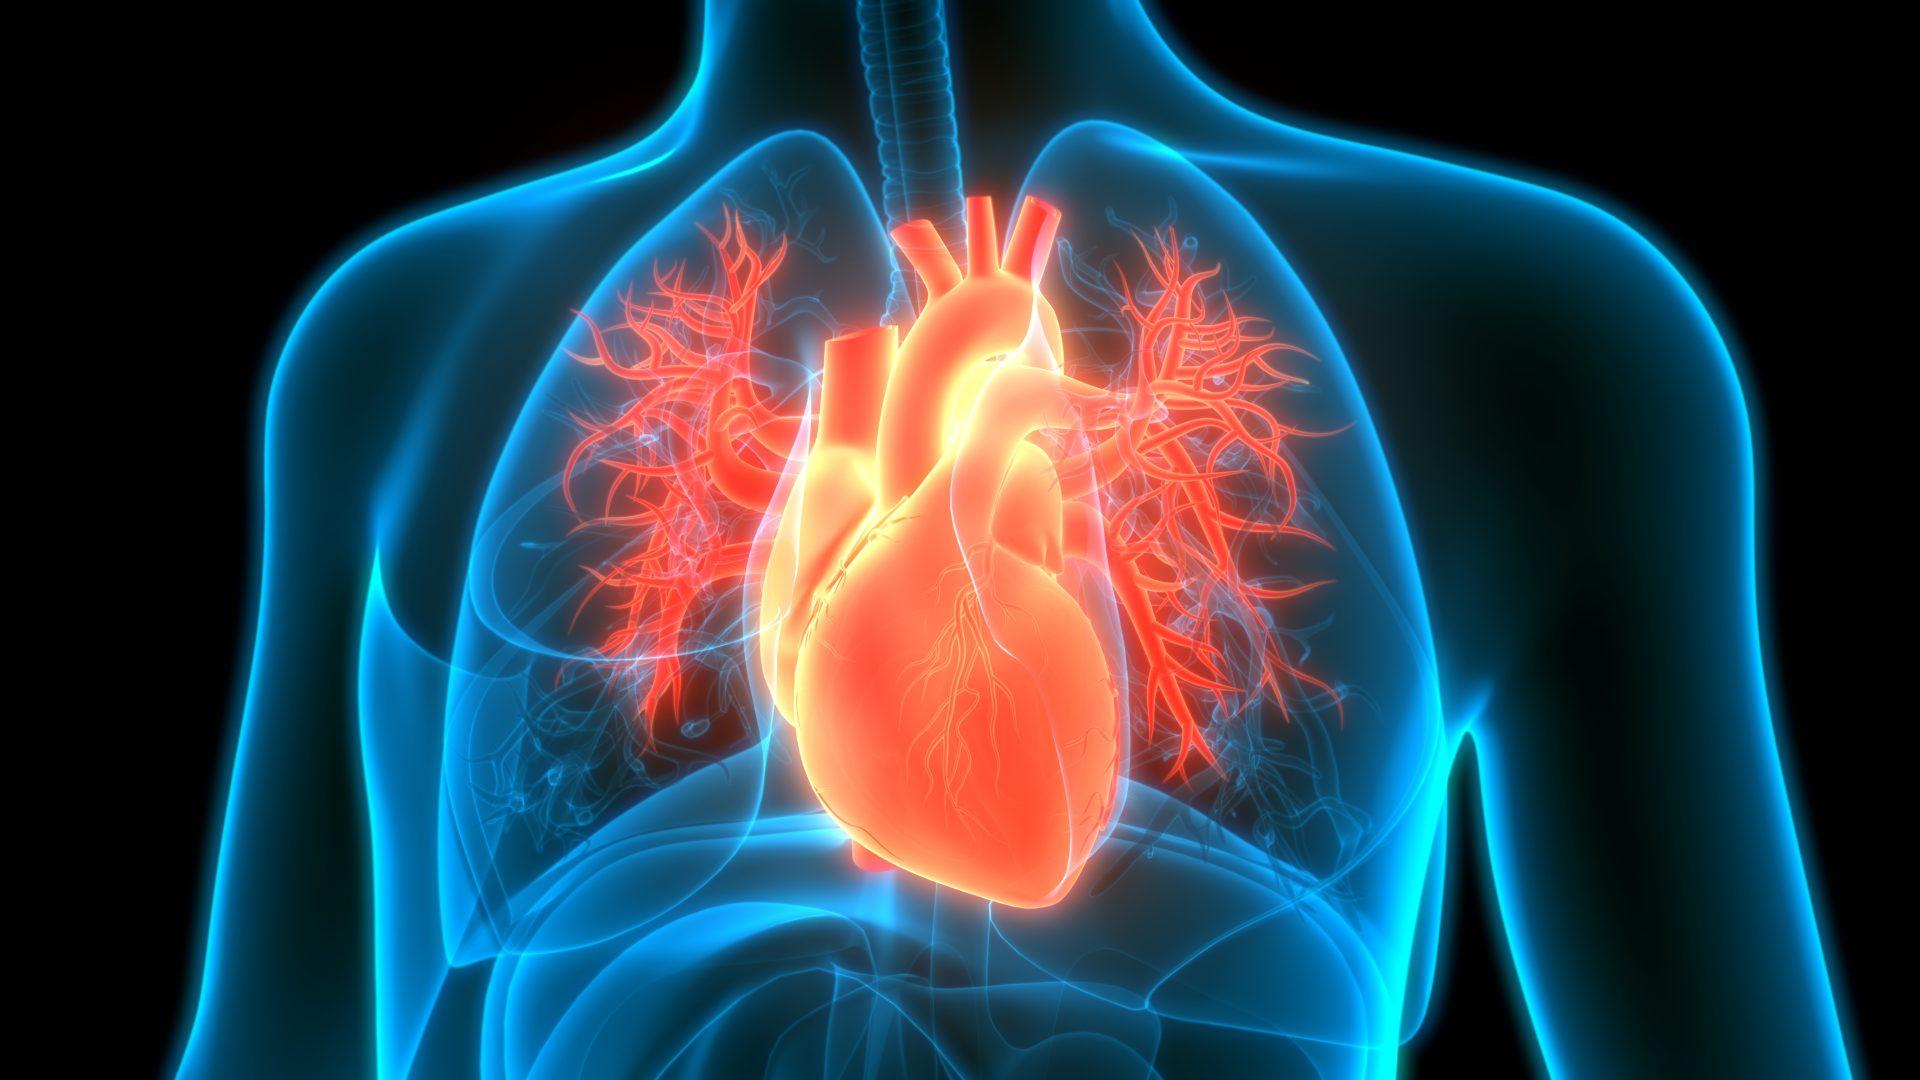

Anatomy and Physiology is a subject that stands out for its significance and potential impact on future careers and understanding of the human body. This course explores the human body’s structure and function, providing an understanding of how our bodies are formed and how they work. Beyond just being a fascinating academic field, anatomy and physiology play a pivotal role in various professions, including medicine, nursing, physical therapy, and more.